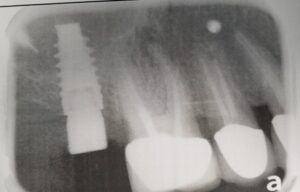

Платформа імпланту NTA implant. З’єднання абатменту розташуване ближче до центру імпланту та подалі від поверхні розділу імплант-кістка. В додаток до наміченого з’єднати, це забезпечує збереження кісткової тканини в процесі служби імпланту (для NTA implant втрати кістки, її розсмоктування є рідкісним явищем).

Платформа імпланту NTA implant. З’єднання абатменту розташуване ближче до центру імпланту та подалі від поверхні розділу імплант-кістка. В додаток до наміченого з’єднання, це забезпечує збереження кісткової тканини в процесі служби імпланту (для NTA implant втрати кістки, її розсмоктування є рідкісним явищем).